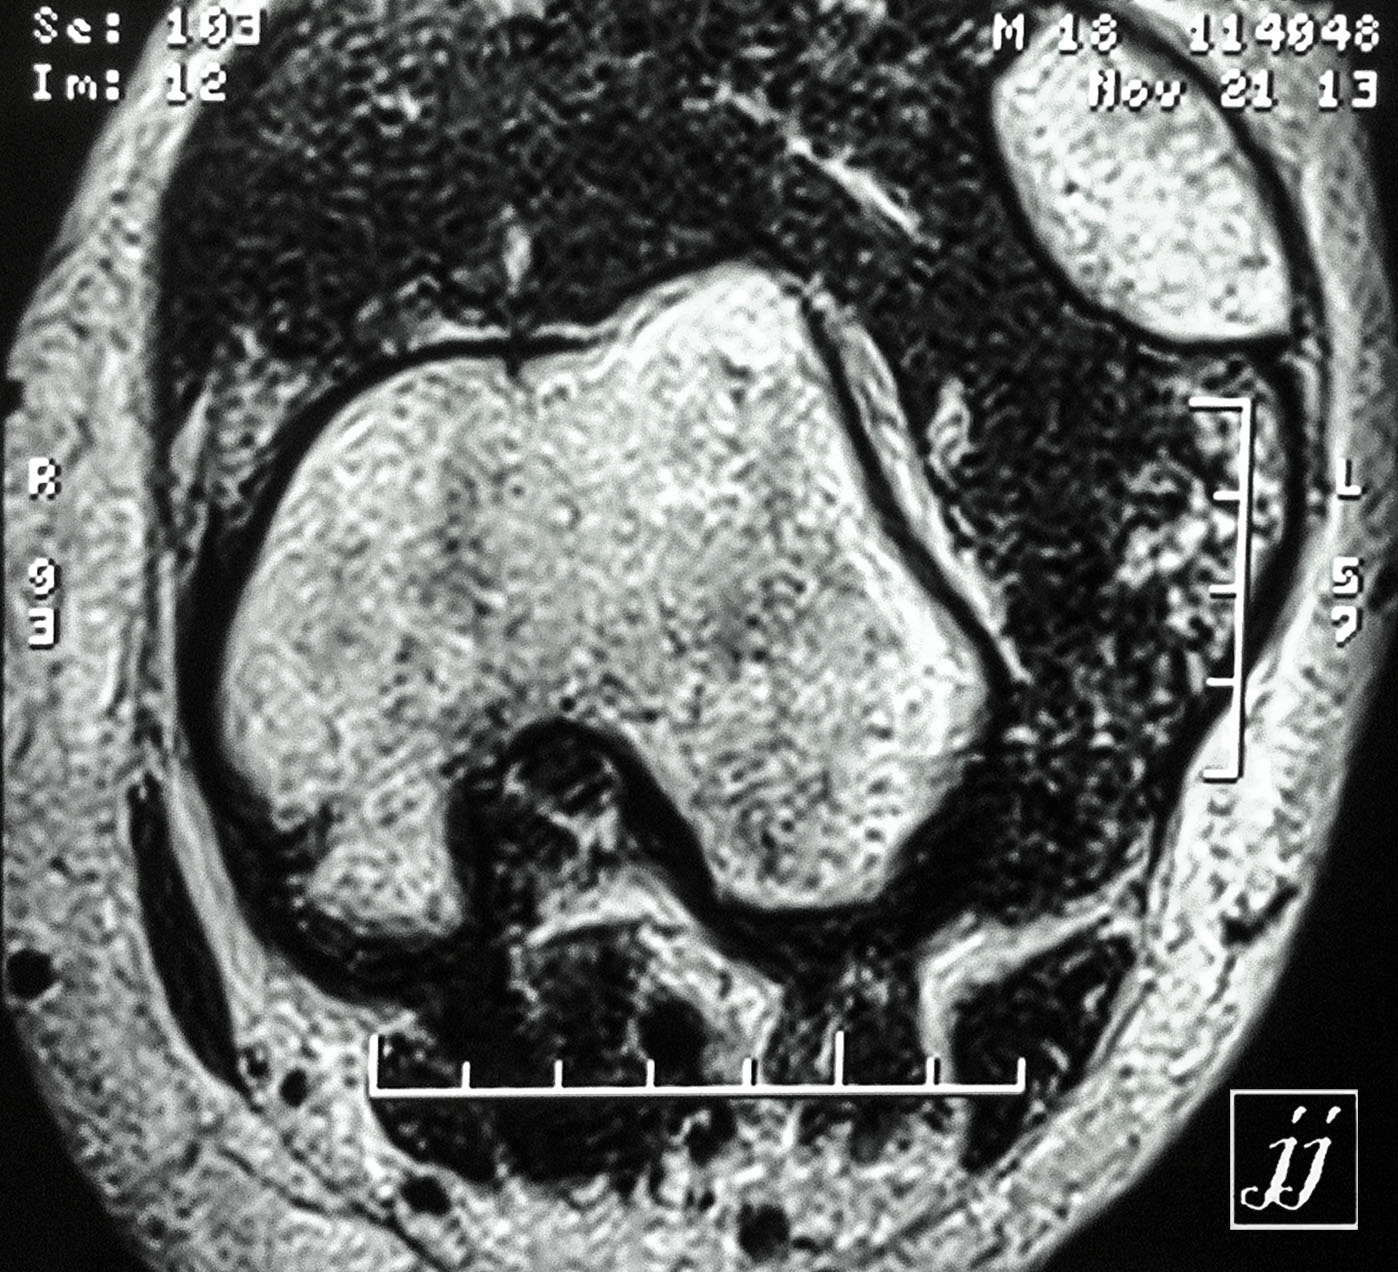

MSK- a tumor in knee joint more likely hemophilia (3)